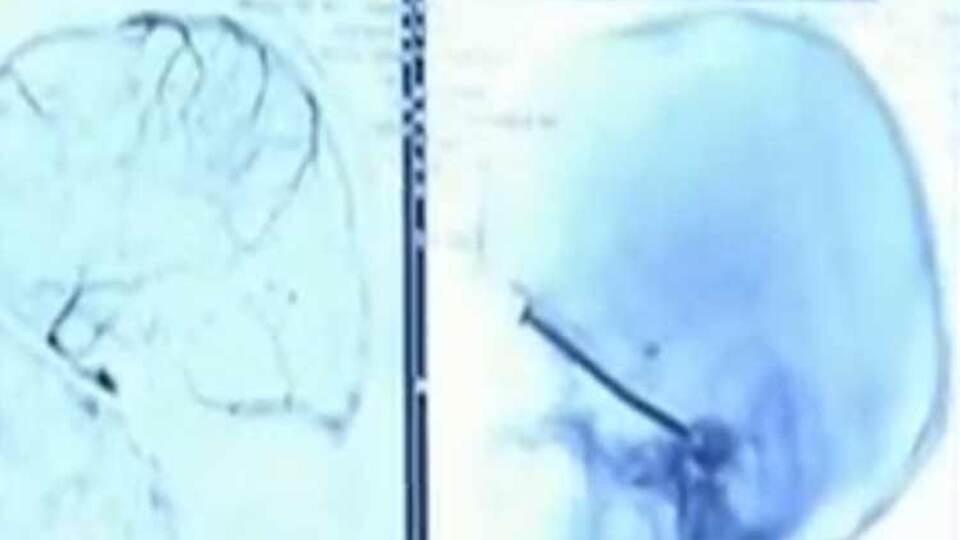

Haberler Dünya Çin'de bir kişinin kafasına 8 santimetrelik çivi saplandı | Dış Haberler

Çin'de başına 8 santimetrelik çivi saplanan kişi zor operasyonun ardından kurtarıldı.

58 yaşındaki Çinli kendini kötü hissedene kadar çivinin kafasına saplandığını fark etmediğini söyledi.